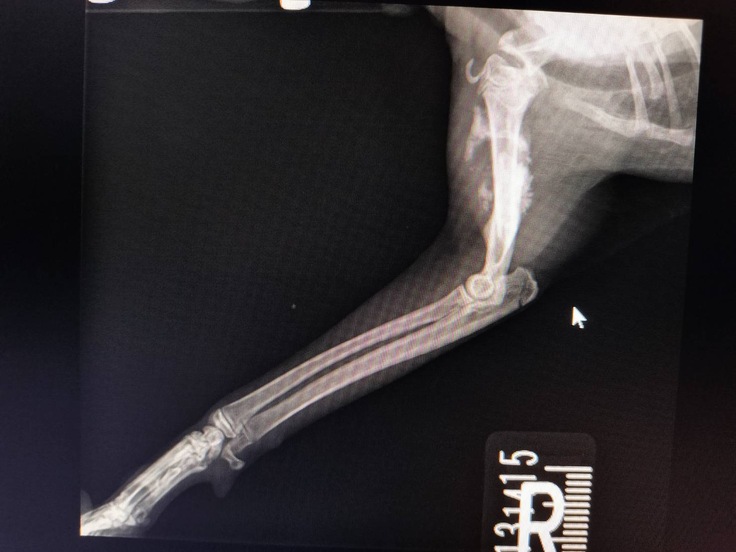

ボッキリ折れた大腿骨

すでに骨がずれたまま、くっつき始めてる